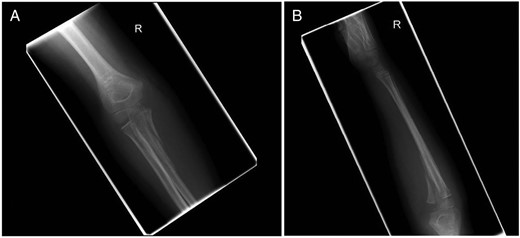

An 8-year-old boy presented with an extension injury to his dominant right elbow, sustained as a result of a fall on a dry ski slope. Examination demonstrated tenderness and swelling of the right proximal forearm with a reduced range of motion. There was no neurological or vascular compromise. Admission radiographs (Fig. 1) and computer tomography scans (Fig. 2) showed a displaced intra-articular, three-part fracture of the right proximal ulna with a fracture line principally in the coronal plane. The radio-capitellar alignment was preserved.

(A) Anterior–posterior radiograph of the elbow and (B) lateral radiograph of the elbow. Admission right elbow radiographs.